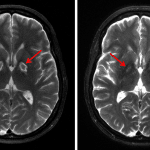

- Symmetric abnormal signal involving the bilateral globi pallidi including central T1/T2 isointensity with peripheral T2/FLAIR hyperintensity, thin discontinuous peripheral T1 hyperintensity, and peripheral enhancement

- Punctate focus of restricted diffusion in the left globus pallidus

- Carbon monoxide toxicity

Symmetric abnormal signal in the bilateral globi pallidi with associated peripheral enhancement as well as patchy cortical enhancement involving the bilateral cerebellar hemispheres, for which the primary differential considerations are a toxic/metabolic process (including carbon monoxide poisoning, cyanide toxicity, and illicit drug use) and subacute infarcts.